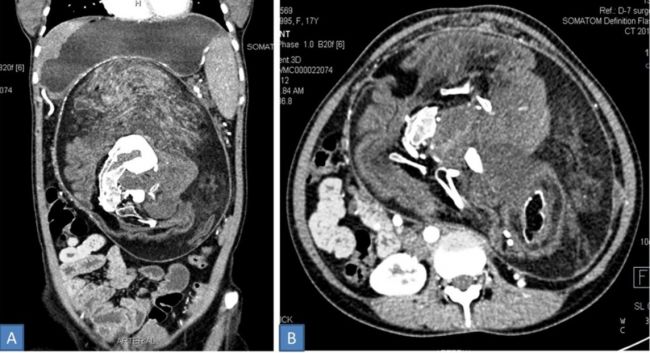

Sau khi tiến hành chụp CT, bác sĩ nhận thấy ổ bụng của cô chứa một lượng lớn xương cốt có cấu trúc tương tự với đốt sống, xương sườn và những đoạn xương dài của cơ thể người. Từ đó, họ kết luận rất có thể cô đã mắc hội chứng “thai trong thai” - một hiện tượng hiếm gặp chỉ xuất hiện với tỷ lệ 1/500.000.

Ảnh chụp CT cho thấy một khối mô chứa lông, tóc, răng và xương trong bụng cô gái trẻ.

Với trường hợp của thiếu nữ trên, cô cần được phẫu thuật cắt bỏ khối u để tiếp tục sinh hoạt bình thường. Khối “thân thể” trong bụng cô gái có kích thước chỉ bằng 2/3 so với một bào thai khỏe mạnh: 36 x 16 x 10 cm, bao phủ bởi lông và mô răng, cùng với các chồi chi chưa kịp thành hình. “Bào thai” này cũng có cả da, tóc và mô mỡ.